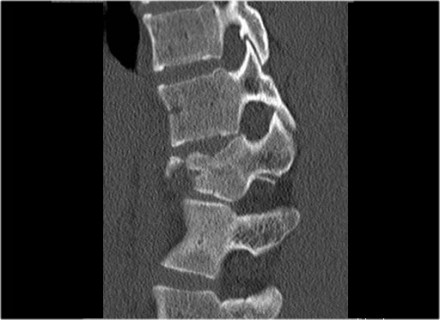

The images are of a patient with a typical bamboo spine as a result of ankylosing spondylitis.

After a fall on his back no fracture was seen on the x-rays.

However the CT shows a thin fracture line through the anterior side of the vertebral body and also through the spinous process.

Continue with the MR-images.